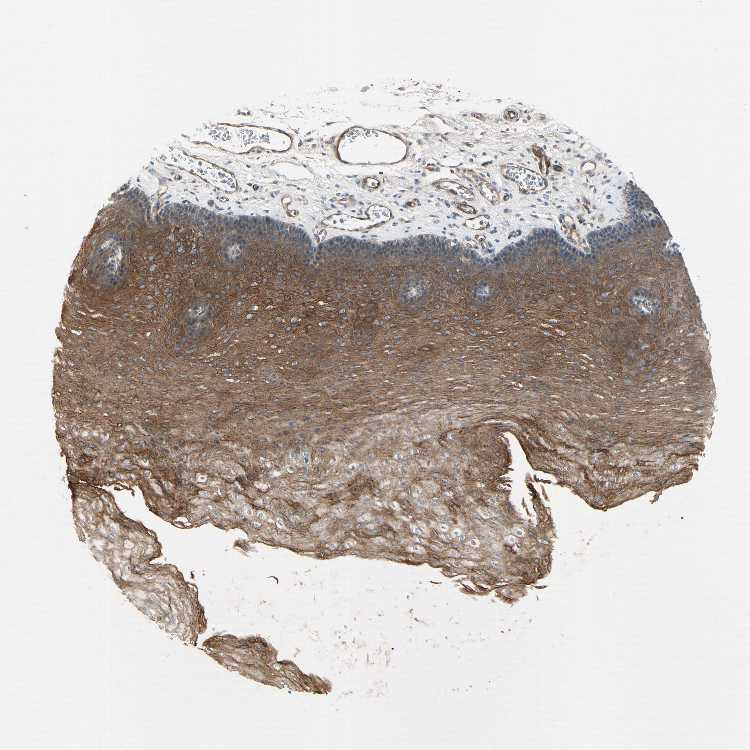

ESOPHAGUS - Antibody stainingi

Antibody staining in the annotated cell types in the current human tissue is reported as not detected, low, medium, or high, based on conventional immunohistochemistry profiling in selected tissues. This score is based on the combination of the staining intensity and fraction of stained cells.

Each image is clickable and will lead to virtual microscopy that enables deeper exploration of all samples and also displays staining intensity scores, fraction scores and subcellular localization as well as patient and tissue information for each sample.

Antibody HPA008233

Squamous epithelial cells Medium